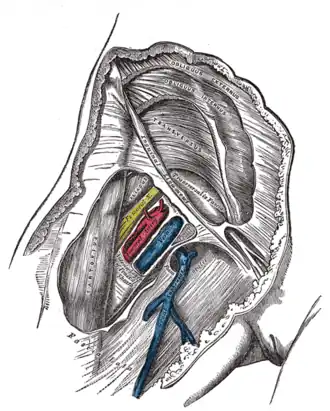

Bainha femoral direita aberta para mostrar seus três compartimentos

O trígono femoral é limitado por:

- ligamento inguinal (superiormente)

- músculo sartório (lateralmente)

- músculo adutor longo (medialmente)

É importante devido ao grande número de estruturas vitais que passam por ali, logo abaixo da pele - mais notavelmente:

- nervo femoral e seus ramos

- bainha femoral e seus conteúdos

- artéria femoral e diversos de seus ramos

- veia femoral e suas tributárias proximais, como as veias safena magna e femoral profunda